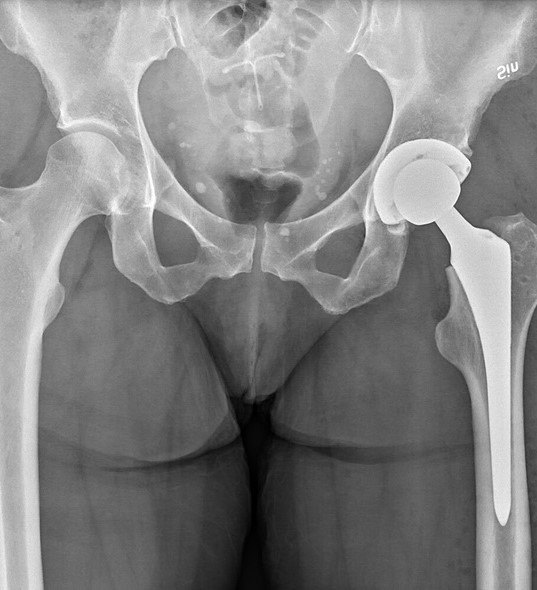

Joint replacement is a highly effective surgical procedure designed to relieve pain and restore mobility in patients suffering from severe joint damage. When joints such as the hip or knee become worn out due to arthritis, injury, or aging, everyday activities like walking, climbing stairs, or even standing can become difficult. Joint replacement surgery replaces the damaged parts of the joint with artificial implants, allowing patients to regain comfort and function in their daily lives.